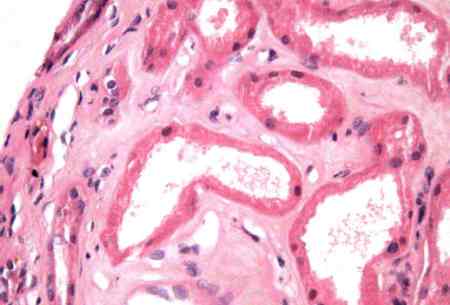

- biopsia renal:

glomérulos de apariencia normal con microscopía óptica con borramiento de procesos podocitarios con microscopia electrónica